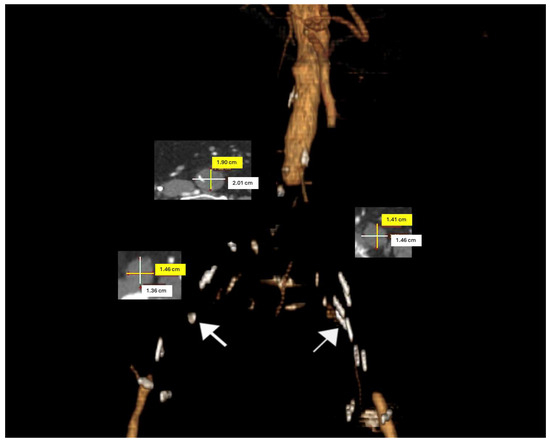

Patients were categorized according to TASC II criteria based on their CTA images. (Figure 1). The American Society of Anesthesiologists (ASA) classification was utilized to assess preoperative physical status and operative risks. Clinical presentations were evaluated using the Rutherford classification. In the absence of contraindications, preoperative dual antiplatelet and statin therapy were initiated and maintained throughout the postoperative period.

Figure 1. A three-dimensional preoperative model of an aorto-occlusive lesion in an 85-year-old male patient. Axial computed tomography angiography (CTA) sections were utilized to measure the diameters of the distal aorta and common iliac arteries. (The white arrows indicate calcifications on the arterial wall).